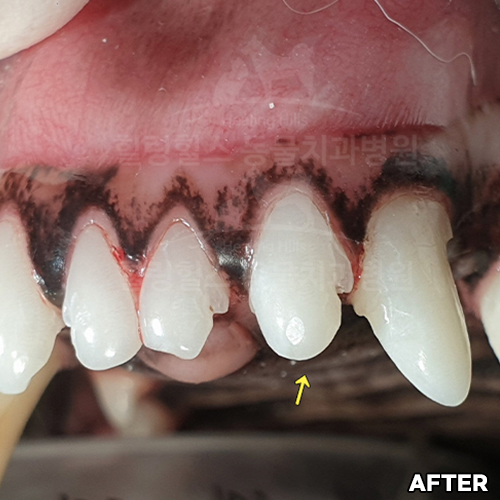

강아지송곳니치주염 치료하고 자라난 잇몸뼈, 빨갛게 부은 잇몸이 좋아진 모습 - 5개월 뒤 덴탈씨티로 확인!